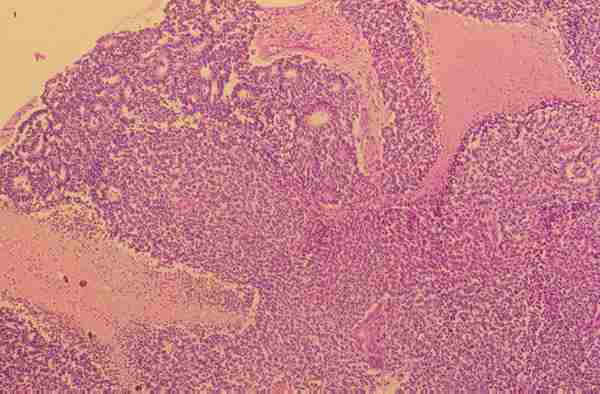

Figura 18. Retinoblastoma masivo que ocupa la cámara vítrea con

mínima regresión (caso n.º10). H.E. (15x).